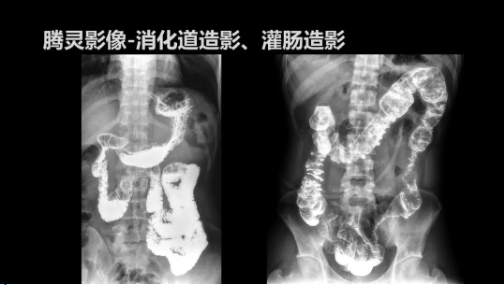

“騰靈”是安健科技的第四代動(dòng)態(tài)DR產(chǎn)品,可實(shí)現(xiàn)全科室應(yīng)用。如各類常規(guī)的X線檢查、消化道檢查、骨科檢查、婦科、兒科檢查等。此外,安健科技為“騰靈”在真正意義上實(shí)現(xiàn)多科室、多功能診斷進(jìn)行了多項(xiàng)針對(duì)性設(shè)計(jì)。

相較前代產(chǎn)品,“騰靈”在圖像質(zhì)量方面得到了全面升級(jí),“騰靈”采用17*17非晶硅平板探測器設(shè)計(jì),采集矩陣達(dá)3072*3072,動(dòng)態(tài)范圍達(dá)16bit,為成像提供超大視野的同時(shí)保證成像質(zhì)量,此外,該款機(jī)型可根據(jù)醫(yī)療機(jī)構(gòu)的差異化需求而選配不同的動(dòng)態(tài)平板探測器,以此來適應(yīng)不同階層用戶所需。

此外,“騰靈”為了能夠幫助醫(yī)生更快速、有效的定位病灶,還增加了多項(xiàng)精準(zhǔn)診斷保障功能,如支持動(dòng)態(tài)觀察診斷,實(shí)時(shí)高清點(diǎn)片等?!膀v靈”透視切換高清點(diǎn)片曝光,捕捉關(guān)鍵病灶診斷僅需0.8s,同時(shí)還支持圖像局部放大,醫(yī)生可自由切換15’12’和9’三種放大模式,另外,“騰靈”還支持視頻保存、回放功能,幫助醫(yī)生在檢查結(jié)束后通過回放查看細(xì)節(jié),為醫(yī)生的診斷增加信心。